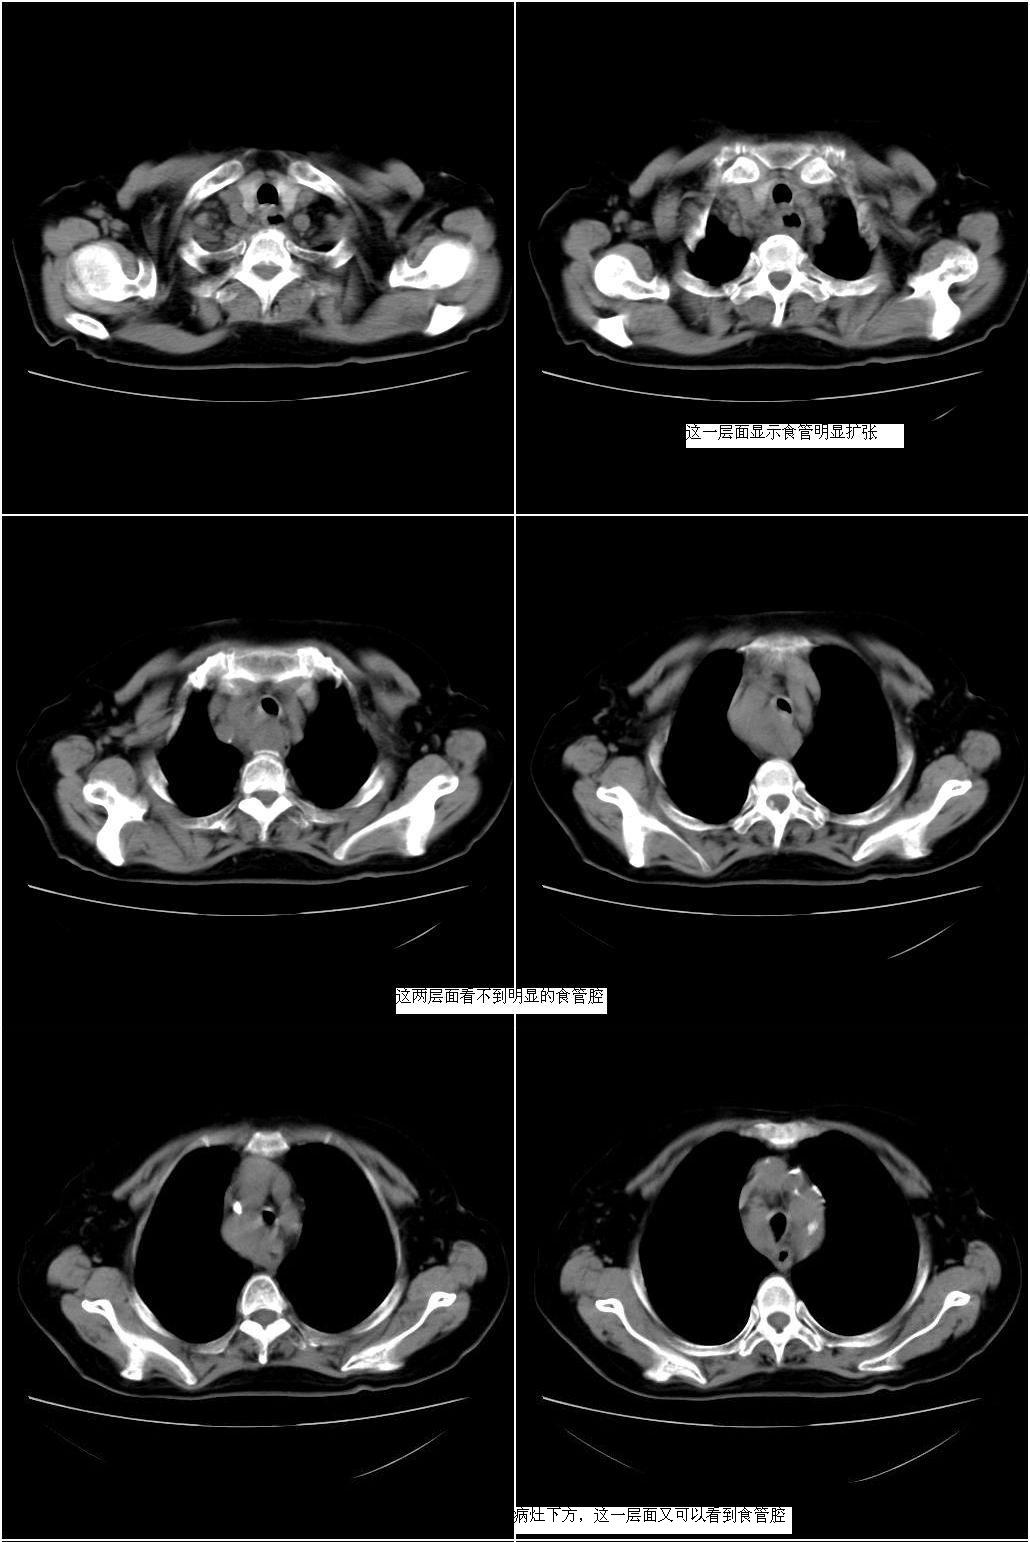

以下是引用sxlcbc在2007-12-23 4:27:00的发言:[br]气管源性肿瘤觉得有点不靠谱啊,看上去气管是受压改变的。更像是上段食管的改变,周围淋巴结肿大,食管受压。看看以下六幅图片:[br]不过,有一点不好理解:食管肿瘤应该有食道症状的,再说食管癌出现周围这么大的淋巴结也不多见啊,如果考虑淋巴瘤倒是更合理一点,这样气管,食管受压改变也许更合理一些。[br][br]